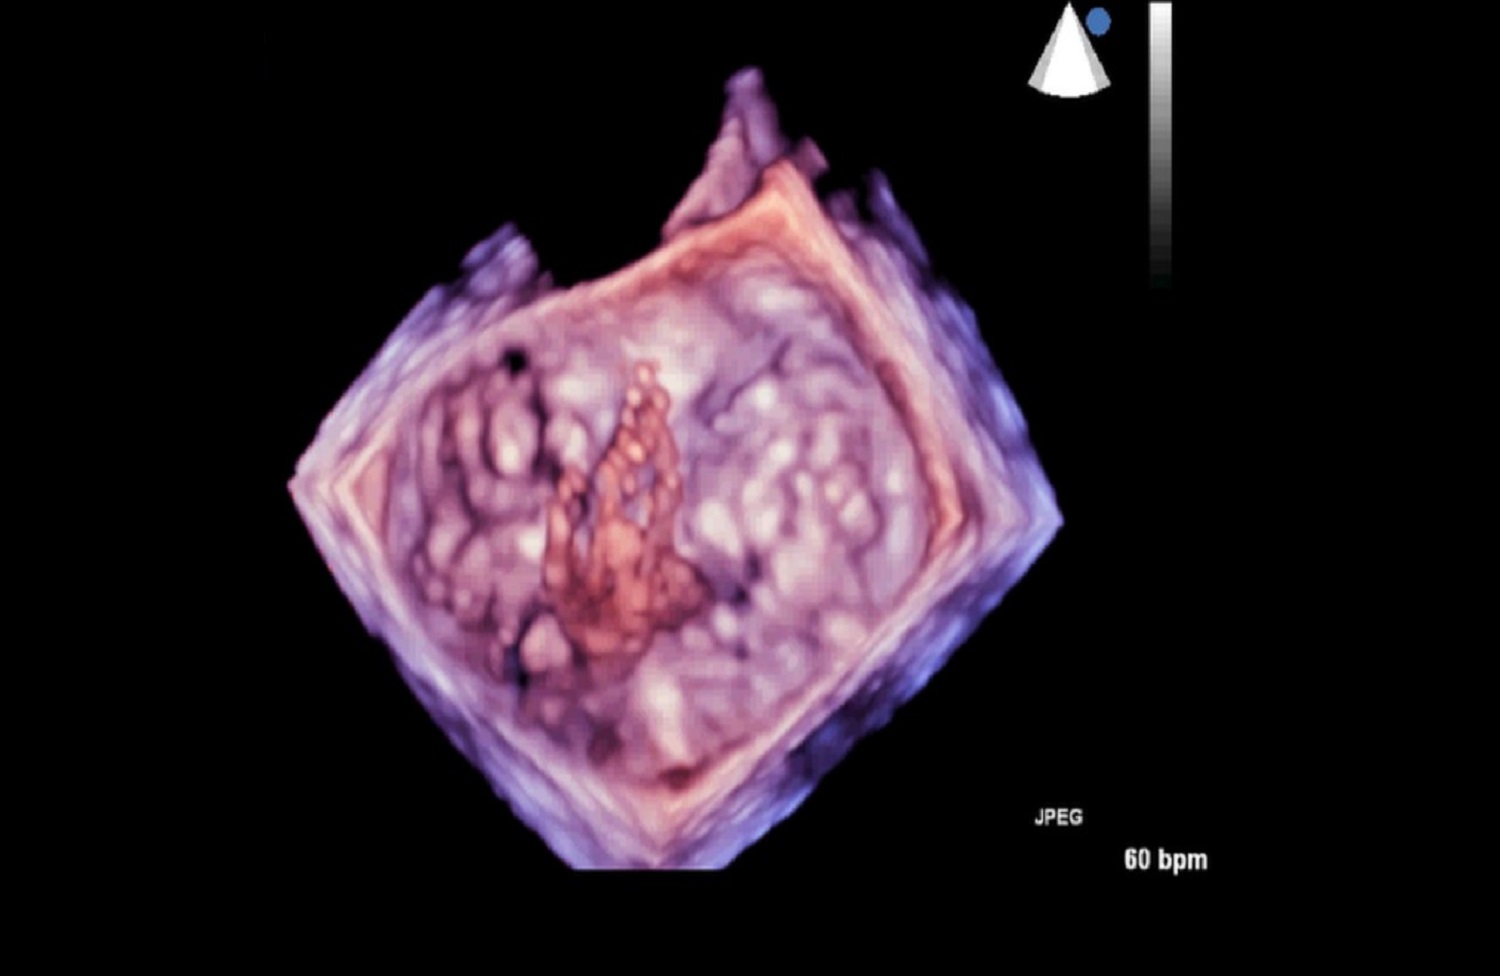

Pracownia Echokardiografii

Pracownia Echokardiograficzna Kliniki posiada Akredytację Klasy C (najwyższy poziom referencyjny) przyznaną przez Zarząd Sekcji Echokardiografii Polskiego Towarzystwa Kardiologicznego. W ciągu roku wykonywanych jest tu łącznie ponad 3600 badań echokardiograficznych przezklatkowych, przezprzełykowych i prób z dobutaminą.

Dzięki wykwalifikowanemu personelowi i nowoczesnemu sprzętowi w Klinice wykonywane są również przezskórne zabiegi zamknięcia ubytków przegrody międzyprzedsionkowej typu II oraz drożnego otworu owalnego, pod kontrolą echokardiografii dwu – i trójwymiarowej.

Na podstawie badań z zastosowaniem przezprzełykowej echokardiografii trójwymiarowej w pracowni kwalifikuje się również pacjentów z ciężką niedomykalnością mitralną w mechanizmie wypadania płatka mitralnego do nowatorskich zabiegów małoinwazyjnej przezkoniuszkowej naprawy zastawki bez użycia krążenia pozaustrojowego. Efektem współpracy z Oddziałem Kardiochirurgii Szpitala Medicover była możliwość monitorowania echokardiograficznego przezprzełykowego dwóch pierwszych w Polsce zabiegów naprawy zastawki mitralnej z użyciem robota chirurgicznego da Vinci.

- Kwalifikacja oraz monitorowanie przy zastosowaniu przezprzełykowej echokardiografii trójwymiarowej nowatorskich zabiegów małoinwazyjnej przezkoniuszkowej naprawy zastawki mitralnej przy zastosowaniu sytemu Neochord.